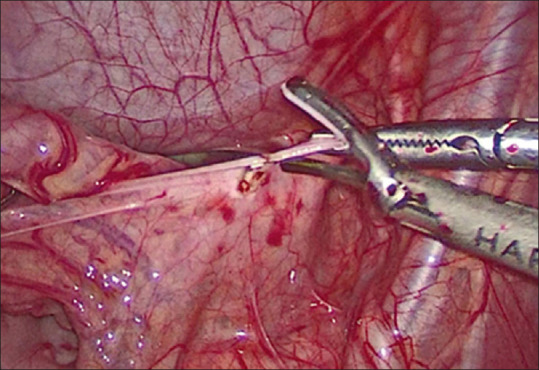

Background: Rectal prolapse is a relatively common, usually self-limiting illness in children. Peak incidence is between 1 and 3 years. The primary treatment of rectal prolapse is non-operative. Surgical intervention is needed in long-standing intractable cases of rectal prolapse, rectal pain/bleeding/ulceration and prolapse that needs frequent manual or difficult reduction. The aim of this study was to compare the efficacy and outcome of laparoscopic ventral mesh rectopexy versus laparoscopic suture rectopexy in the management of persistent rectal prolapse in children not responding to conservative management and/or recurrent after sclerotherapy or anal encirclement.

Materials and methods: Twenty-four cases were randomised into two groups at the ratio of 1:1, Group 1 patients were managed by laparoscopic ventral mesh rectopexy, whereas Group 2 cases were managed by laparoscopic suture rectopexy. Patients with primary surgical conditions such as anorectal malformations, Hirschsprung's disease, rectal polyps or masses and Ectopia Vesicae were excluded from the study. Inclusion criteria were complete rectal prolapse cases with failed medical treatment for at least 6 months and/or recurrent after injection sclerotherapy or anal encirclement.